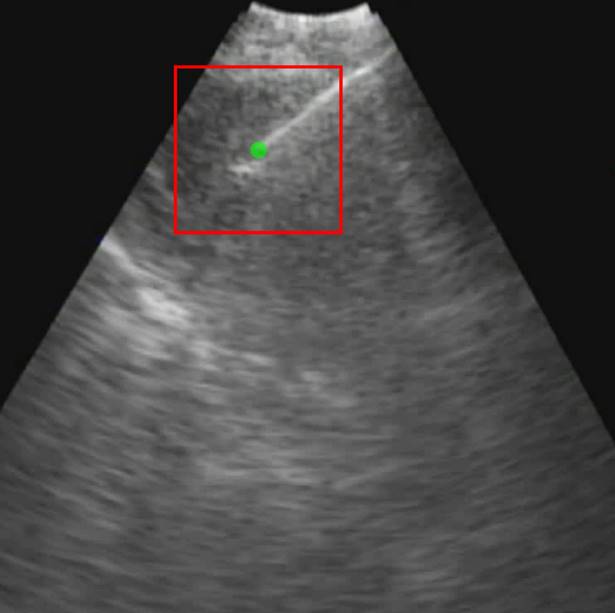

Each video was analyzed within a mathematical programming environment with custom-designed software (MatLab 2020, The MathWorks, Natick, MA). The position of the needle tip in each video was manually identified, and a J Cancer inline graphic cm J Cancer inline graphic pixel region of interest (large enough to encompass the bolus of injected drug) was centered on the needle tip (Figure 1).

Figure 1

Initial frame from an EBUS image (B11). The green dot is the manually identified needle tip position centered within a 1 cm x 1 cm region of interest (red square). The tics along the right and bottom edges are separated by 5 mm.